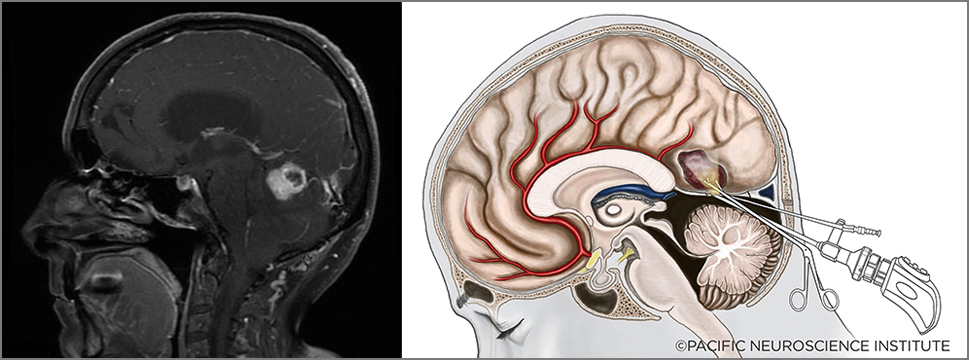

Hemangioblastoma